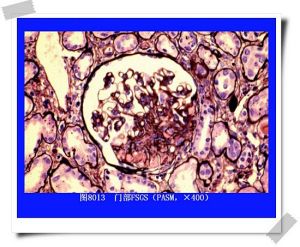

隱匿性腎小球疾病患者的腎臟病理改變多種多樣。現以局灶性腎小球腎炎伴復發性血尿為例介紹如下:

根據腎穿刺活組織檢查,顯示腎小球有輕微增生 性病 變,通常只散在累及腎小球的一個節段,且病變呈局灶性分布。基膜常無病變發現,腎小球系膜細胞常有不同程度的增生。免疫螢光研究主要在腎小球系膜部分可見有IgA沉積,有時尚同時有IgG和補體C3之沉積。電鏡下可見“駝峰”樣電子緻密物質沉積於上皮或內皮下及系膜中。